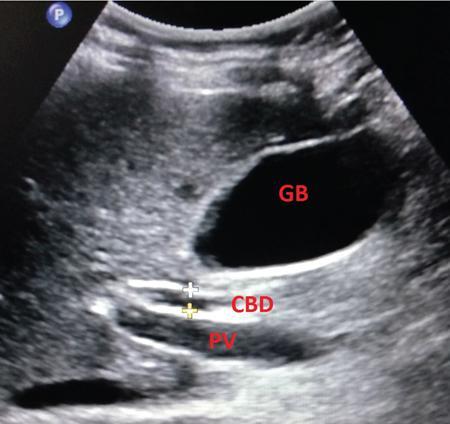

Samarjit Ghuman, Seema Sud, Deeksha Rastogi, Swapnil Sheth, T.B.S. Buxi PLAIN RADIOGRAPHY FOR HEPATOBILIARY IMAGING The diagnostic imaging techniques for hepatobiliary imaging can be intimidating with many techniques/modalities providing the information desired. The job of the diagnostic radiologist includes being familiar with the available choices and pick the ‘best fit’ keeping in mind the pros and cons of each modality, which includes plain X rays, Contrast studies using plain X rays and fluoroscopy, Ultrasound includiojng Doppler and Ultrasound elsastography, CT including multiphase CT and MRI and MRI elastography. Understanding the strengths and weaknesses of every modality as well as the ability to tailor each study individually will help to optimise patient cares. The abdominal radiograph is performed almost exclusively in the supine position and in the AP (anteroposterior) projection. In case of acute abdomen, an erect chest radiograph should also be performed to look for free air under the diaphragm. The standard abdominal radiograph should extend from the diaphragm to the inferior pubic rami, and includes the lateral abdominal wall musculature. Routinely no preparation is required for abdomen radiograph done for hepatobiliary imaging. The radiograph has limited soft-tissue contrast, however, the liver being the largest intra-abdominal organ, casts a perceptible shadow. The margins of the liver can indirectly be seen by outline of adjacent organs like lung, hemidiaphragm, pro-peritoneal fat line, kidney and gas shadows of stomach/colon. The right lobe is seen better than the left lobe of liver. The following pathologies may be visualized on the plain radiograph of the liver. Liver enlargement Liver mass Calcification Increased radiodensity of the liver Decreased radiodensity of the liver An ultrasound is the first line investigation; however, a radiograph may be done for routine evaluation of abdominal pain. The following pathologies may be seen on plain radiograph of the biliary tree. Calculi and Calcifications Gas ULTRASOUND OF HEPATOBILIARY SYSTEM Ultrasonography (USG) is the initial imaging modality of choice for scanning hepatobiliary system. USG is accurate and has high sensitivity and specificity in diagnosing biliary pathologies. Table 9.1.1 shows indications of ultrasound in hepatobiliary system. The real-time nature of ultrasound lends itself to demonstrate mobility of calculi and sludge and the sonographic Murphy sign can easily be elicited during scanning. The main disadvantage is operator dependence, patient’s body habitus, presence of gas which can obscure the visualization of organs, overlying bandages in a postoperative patient and incomplete evaluation in a nonfasting state. USG of upper abdomen should be done after 6–8 hours of overnight fasting. Milk and fatty food should be avoided as they cause contraction of the GB and may cause the GB walls to appear thickened. History of previous surgery, especially cholecystectomy should be elicited. The patient may be positioned in supine or left lateral decubitus position. The GB can be scanned from a high/lateral view, looking through the ribs in supine position or through a sub-costal view in left lateral decubitus position. Position of patient may be changed to demonstrate mobility of structures. The GB is an anechoic structure which is located in the GB fossa along the posterior and inferior aspect of the liver. It has a fundus, body and a neck. It should always be examined in at least two planes (Fig. 9.1.6A and B). The wall of the normal GB should measure 3 mm or less and pathological GB wall thickening can be due to cholecystitis or a neoplastic aetiology. Calculi appear as mobile hyperechoic foci, with distal acoustic shadowing. Other pathologies include polyps and sludge which can be differentiated on the basis of their mobility. The CBD measures less than 6 mm in diameter with increase in the diameter with patient’s age and after cholecystectomy. The CBD is usually scanned in an oblique subcostal plane with the patient in the left decubitus position (Fig. 9.1.7). Dilatation of the intrahepatic biliary radicles is readily assessed with USG and normal intrahepatic biliary radicles are usually not appreciated on USG. Ultrasound of the liver, broadly, is done to assess the size, surface (smooth, coarse or lobulated) parenchymal echogenicity (increased or decreased) vascularity and for presence and evaluation of intrahepatic masses or fluid collections. The liver is divided into right and left lobes by plane of middle hepatic vein which passes through GB fossa and notch of IVC (Cantlie Line). Couinauds classification is the most commonly used system for liver segmental anatomy and described liver into eight functional segments. It is based on distribution of portal and hepatic veins. Every segment has its branch from portal vein, hepatic artery and bile duct (Fig. 9.1.8). Curvilinear transducer (3–5 MHz) is used for routine examination of liver and GB (Fig. 9.1.9). A high-frequency linear transducer (9–11 MHz) (Fig. 9.1.10) can be used to look for subtle irregularity of the liver surface for early Cirrhosis and fine details of GB wall. The liver is scanned in deep inspiration, which causes inferior movement of liver, so that superior borders of the liver are well visualized. Supine position is used for the size of the liver. The measurement is made in sagittal mid clavicular position on right side, in craniocaudal dimension. It is taken from diaphragm to the lower end of the liver. It should be <16 cm and varies with age and sex. The liver is divided into four vertical sectors by three hepatic veins and plane of bifurcation of portal vein divides these 4 sectors in to 8 segments. The right hepatic vein creates vertical plane in the right lobe separating segments V and VIII (anterior) from VI and VII (posterior). The portal vein bifurcation creates a transverse plane and divides these segments into superior (VII, VIII) and inferior segments (V, VI). The left hepatic vein divides the left lobe into medial (IVa, IVb) and lateral sectors (II, III). The left portal vein divides left lobe into superior (Iva, II) and inferior segments (III, IVb). The middle hepatic vein separates medial segments of left lobe (IVa, IVb) from anterior segments of right lobe (V, VIII). Ligamentum teres separates segment III from IVb. Ligamentum venosum separates segment I from IV and II. Cystic duct is an anechoic tubular structure which connects neck of the GB to the extrahepatic biliary tree. In long axis view of GB, the neck of the GB is related to main lobar fissure which appears as a linear echogenic line which runs obliquely between neck of GB and right portal vein. In the right oblique sub coastal view CBD is seen anterior and parallel to portal vein. A series of standardized sections or views may be obtained for liver scanning. Transverse Subcostal View: In this view the probe is angled cephalic and placed transversely under the ribs on the right side and portions both lobes of the liver can be seen (Fig. 9.1.11). Mid Transverse View (Fig. 9.1.12) in this transducer is kept in transverse plane in the midline below the xiphisternum. It visualises the liver in an inferior to superior transverse oblique plane and portions of both lobes of liver can be seen along with right and left portal veins. This view is obtained by angling the transducer superiorly toward the hepatic venous confluence. In this view, we can see the three hepatic veins joining the IVC. Right Parasagittal View for Both Right Lobe and Kidney: This view allows assessment of inferior right lobe of liver. It also allows assessment of relative echogenicity of liver and renal cortex as both are seen together in the same image. Normal liver parenchymal echogenicity is greater than renal cortex and less that renal medulla (Fig. 9.1.14). Parasagittal Right MidClavicular View: In this transducer is kept in sagittal plane in right midclavicular line, and oriented supero-inferiorly. This is the standard view for assessing craniocaudal span of liver (Fig. 9.1.15). Parasagittal View for the Left Lobe: For evaluation of left lobe of liver and lateral segments (2 and 3) (Fig. 9.1.16). This view is obtained along the direction of the main portal vein. CEUS of the liver is done to evaluate Focal Liver Lesions and complements traditional B mode ultrasound and Doppler study. It is a simple, accurate and cost-effective tool complimenting indeterminate CT and MRI findings or for characterization of lesions in patients who cannot receive CT/MRI contrast and can be used in patients with compromised renal function, with minuscule risk of side effects. As CEUS is real-time, microvasculature can be studied along with tissue perfusion kinetics. Indications and uses of CEUS: Contrast agents and technique: Interpretation: Contrast-enhanced ultrasound of a hepatic hemangioma in different phases (Fig. 9.1.19). Limitations of CEUS: Liver elastography is a noninvasive method for diagnosing liver fibrosis. Liver fibrosis is induced by chronic liver disease leading to cirrhosis and liver cancer. Liver biopsy is the gold standard for diagnosing the degree of fibrosis and for staging but it is an invasive method. Elastography helps in analysing the elasticity or the stiffness of the tissue. A stiffer liver tissue indicates fibrosis or chronic liver disease. ARFI is based on the principle of measuring Shear wave velocity. Short duration acoustic pulses which are generated in the tissue and these give rise to shear waves which travel, perpendicular to the ultrasound beam. These shear waves cause tissue displacement followed by recovery. This displacement and recovery depend on tissue stiffness. To monitor these shear waves US beams of low intensity are emitted continuously parallel to the main beam along with the push pulses, and these beams can gather data regarding the tissue stiffness. The shear waves cause tissue displacement and this tissue then recovers from the impulse. From this data the degree of tissue stiffness can be obtained which is displayed either as a map or quantitatively where tissue elasticity is expressed as shear wave velocity measured in meters per second. F0, normal; F1, enlarged fibrotic portal tract; F2, periportal/initial porto-portal septa with intact architecture; F3, architectural distortion with no obvious cirrhosis; F4, cirrhosis. It is also known as Transient Elastography (TE) and works on the similar principle as ARFI, the difference being that B mode ultrasound image is not produced. DOPPLER OF PORTAL VEIN The portal vein divides at the portahepatis into right and left branches. The right portal vein divides into anterior and posterior branches, and the left portal vein divides into medial and lateral branches. Portal vein shows a continuous, forward low-velocity flow (15–28 cm/s) on colour Doppler scanning. The flow is hepatopetal, that is, towards liver and is red in colour as it is flowing towards the transducer. It has an undulating pattern and shows respiratory variation with increase flow in inspiration. It may reflect cardiac variation and shows postprandial increase calibre and flow in healthy individuals. Normal Doppler waveform of portal vein (Fig. 9.1.22). Portal hypertension can be defined as elevated pressure within the portal venous system resulting in impaired blood flow through the liver. INTRAOPERATIVE PANCREATIC AND HEPATIC ULTRASOUND Intraoperative ultrasonography of the pancreas was first described in 1980 by Lane and Glazer. It is an important technique for guidance of both open and laparoscopic surgical procedures of the pancreas. As the transducer is in direct contact with the organ of interest, with no interference with air of adjacent soft tissue, it provides good resolution. It is considered superior to CT and MRI in assessing the intraoperative tumour resectability and vascular invasion and guiding resection. Indications and uses For intraoperative US during open surgical procedures, a high-frequency linear-array transducer or the hockey stick transducer (Fig. 9.1.23) are used which create high-resolution detail of the exposed pancreas. The side-fire curved linear-array transducer is effective for obtaining a wider view of the pancreas and its surrounding structures and for scanning the liver. Intraoperative hepatic ultrasound gives the real-time visualization of the hepatic anatomy and aid for surgical planning and making decision during surgery. Indications and uses Transducer and technique Limitations MULTIDETECTOR CT OF THE HEPATOBILIARY SYSTEM AND CHOLANGIOGRAPHY The cross-sectional plane of the patient is denoted as the x/y plane. The plane along which the table moves is the ‘z’ plane. Multidetector CT denotes more than one detector along the Z-axis, with the latest machines having up to 320 and now even 640 rows of detectors. This provides CT with very fast, high resolution, isotropic images which can be reconstructed in any plane or even curved planes. MDCT scanners can comfortably scan the entire abdomen in 10 seconds or less, thereby allowing visualization of different phases of contrast enhancement. Contrast Media (CM) after administration gets distributed from the intravascular compartment into the interstitial spaces. Intravascular arterial enhancement (for angiography) and parenchymal enhancement have different kinetics. Parenchymal enhancement is directly proportional to total iodine dose being administered and inversely proportional to weight, which is a marker of extracellular volume into which contrast redistributes. Rate of iodine administration has no effect on degree of parenchymal enhancement. As a general rule approx. 500–600 mg of iodine/kg body weight achieves adequate hepatic parenchymal enhancement. For a 60 kg adult, this translates into approx. 100–120 mL of contrast containing 300 mg of iodine per mL. Intravascular or arterial enhancement is controlled by rate at which iodine is administered (flow rate and iodine concentration of CM) iodine flux and duration for which contrast is administered longer injection also leads to better overall arterial opacification due to recirculation effects. This principle is made use of while performing abdominal CT Angiography. Higher iodine delivery rate per unit time using a higher iodine concentration contrast medium also improves conspicuity of vessels and hypervascular lesions such as HCC. For identical parameters, difference in arterial enhancement between patients is dependent on cardiac output with enhancement being inversely proportional to cardiac output. For optimal imaging and enhancement, in multiphase imaging and angiographic studies, contrast material administration and parenchymal or vascular enhancement must be synchronized with CT data acquisition. The two main methods are: Test bolus technique: A test dose of contrast is given and the time to peak enhancement is measured in a ROI placed in a target vessel this information can be used to tailor CT acquisition. Automated bolus Triggering: ROI is placed in target vessel (usually aorta at level of diaphragm) on a plain image. While CM is injected, a series of low dose scans is obtained through the ROI. When the density of contrast reaches a predefined threshold (e.g. 150 HU), at time ‘t’ the scan is automatically triggered. The trigger delay after time ‘t’ is a minimum of 2 sec, and can be programmed to any value. Bolus tracking is nowadays the method of choice for planning contrast medium administration and this technique provides more homogenous opacification. Saline chase is recommended in all multiphase protocols. Significant amount of contrast may be present in the peripheral veins after injection of IV contrast and use of saline chaser leads to better vascular enhancement and lower overall contrast dose (Fig. 9.1.24). Using the above, a standard sequence of acquisitions and contrast enhancement techniques can be tailored to the pathology and organ of interest and pre-programmed into the scanner menu, which includes kVp, mAs, pitch, rotation time, slice thickness etc. This is known as a scan protocol. However, these can be modified as necessary. For example, rotation time can be shortened and pitch can be increased for breathless patients to reduce scan times (Table 9.1.4). Multidetector CT is the workhorse of hepatobiliary imaging. It plays a major role in imaging congenital, traumatic, infective, neoplastic and vascular pathologies of the hepatobiliary system. Scans can be obtained with or without intravenous (IV) iodinated contrast material administration. Multidetector CT scanners are capable of imaging multiple phases at different points of time following injection of contrast and provide dynamic imaging due to fast scan times and rapid coverage of the abdomen. Indications for liver imaging include, but are not limited to: Unenhanced Scan: Hepatic fat estimation, radio opaque biliary calculi. Single Phase Scans: Liver abscess, polytrauma, follow up of known oncologic or benign lesions, abdominal pain, suspected cholecystitis. Multiphase Studies: Evaluation of hepatic masses, imaging in cirrhosis, imaging for resectability, liver donor evaluation, malignancy of GB, hepatic venous outflow obstruction etc. CT Angiography of Hepatic Vessels: Trauma, vasculitis, post-operative bleeding and as a part of multiphase studies. Depending on the indication, scanning protocols can be tailored to highlight the suspected pathology and provide relevant answers for further management (Table 9.1.5). The liver has a dual blood supply, most of which is derived from the portal vein. After injection of contrast, until the portal vein provides recirculated contrast material filled blood to enhance the hepatic parenchyma, the hepatic parenchymal enhancement is relatively poor and dependent only on the hepatic artery. The hepatic arterial phase can be divided into an early arterial phase without any portal opacification, a late arterial or portal inflow phase in which there is some portal vein opacification. This is followed by a portal venous phase in which portal and hepatic veins are enhanced (also called the hepatic venous phase in some articles). In addition, an unenhanced/plain scan and an equilibrium phase can also be acquired. Tumour conspicuity of hypervascular lesions was found to be best on the late arterial or portal inflow phase (Fig. 9.1.25). The early arterial phase is seen up to 10 seconds after trigger, and provides ‘angiographic’ images of hepatic arterial anatomy. This phase is used to provide details regarding arterial anatomy and morphology. Later arterial phase 18–23 seconds, portal venous phase 60–70 seconds and equilibrium phase 180 seconds are obtained after trigger. Equilibrium phase images have been shown to increase detection of hepatocellular carcinoma in cirrhotic patients. The portal venous phase is the standard phase for routine chest/abdomen survey and follow up of hepatic abscesses and hypovascular metastases. Single Phase Scan Protocol: Oncologic follow-up, Liver Abscess – For routine single-phase CT, contrast as per body weight can be injected over 40 seconds and scanning can be done after an empiric delay of 70 seconds from the beginning of injection. This protocol provides good parenchymal enhancement and portal and hepatic vein visualization. Plain scan is optional. Dual-Phase Scan Protocol: Hepatic evaluation in patients with malignancies known to have hypervascular metastases – Neuroendocrine tumours, renal cell carcinoma, thyroid carcinoma, (.) melanoma etc. Late arterial Phase 20–22 seconds and Portal venous phase at 60–70. Plain scan optional. Hepatic Resection Protocol: For patients with known hepatic mass being evaluated for resection. Early arterial phase provides pure arterial or angiographic images. It is obtained at 8–10 seconds post trigger followed by portal venous phase at 60–70 seconds. This is required for arterial and venous anatomy and volumetric evaluation if required. Plain scan is not required. In case a hepatic mass needs characterization as well as resectability planning, late arterial and equilibrium scans may also be done. Indications for angiography are further discussed in the section on angiography. The same biphasic protocol using angiography or arterial phase images is used in patients with trauma suspected to have pseudoaneurysms, hepatic artery thrombosis or dissection in transplant recipients, evaluation of living donors and in patients in whom an angiographic ‘road map’ is required prior to intervention. Triphasic or 4 phase scan Protocol: Standard of care for patients with cirrhosis being evaluated for Hepatocellular carcinoma and for patients being evaluated for hepatic mass of uncertain aetiology. Late arterial phase scan: 20–22 seconds, Portal venous scan at 60–70 seconds and Equilibrium scan at 180 seconds. Plains scans are optional. Our institutional practice is to always do plain scans in patients who have undergone hepatic intervention. Plain scans also help to visualize siderotic and steatotic nodules. A further delayed scan is suggested by some authors at 10–15 minutes for characterization of hepatic masses of uncertain provenance. This is particularly useful in cholangiocarcinoma (Table 9.1.6).

Gallbladder and biliary tree